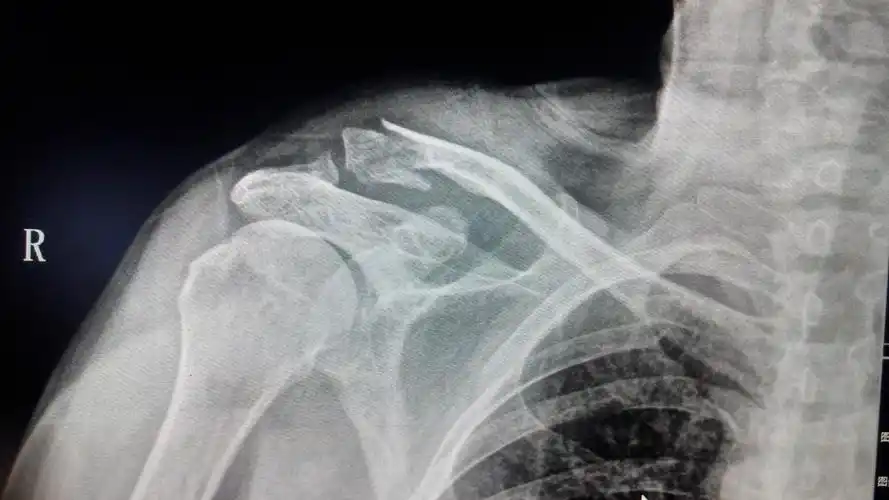

左锁骨肩峰端骨折

我骑车不慎将左侧肩膀摔伤,去医院拍片诊断为左侧锁骨肩峰端骨折,10

锁骨肩峰端骨折钩板固定

锁骨肩峰端骨折~锁骨钩板固定

锁骨肩峰端骨折,第一次使用钩钢板手术